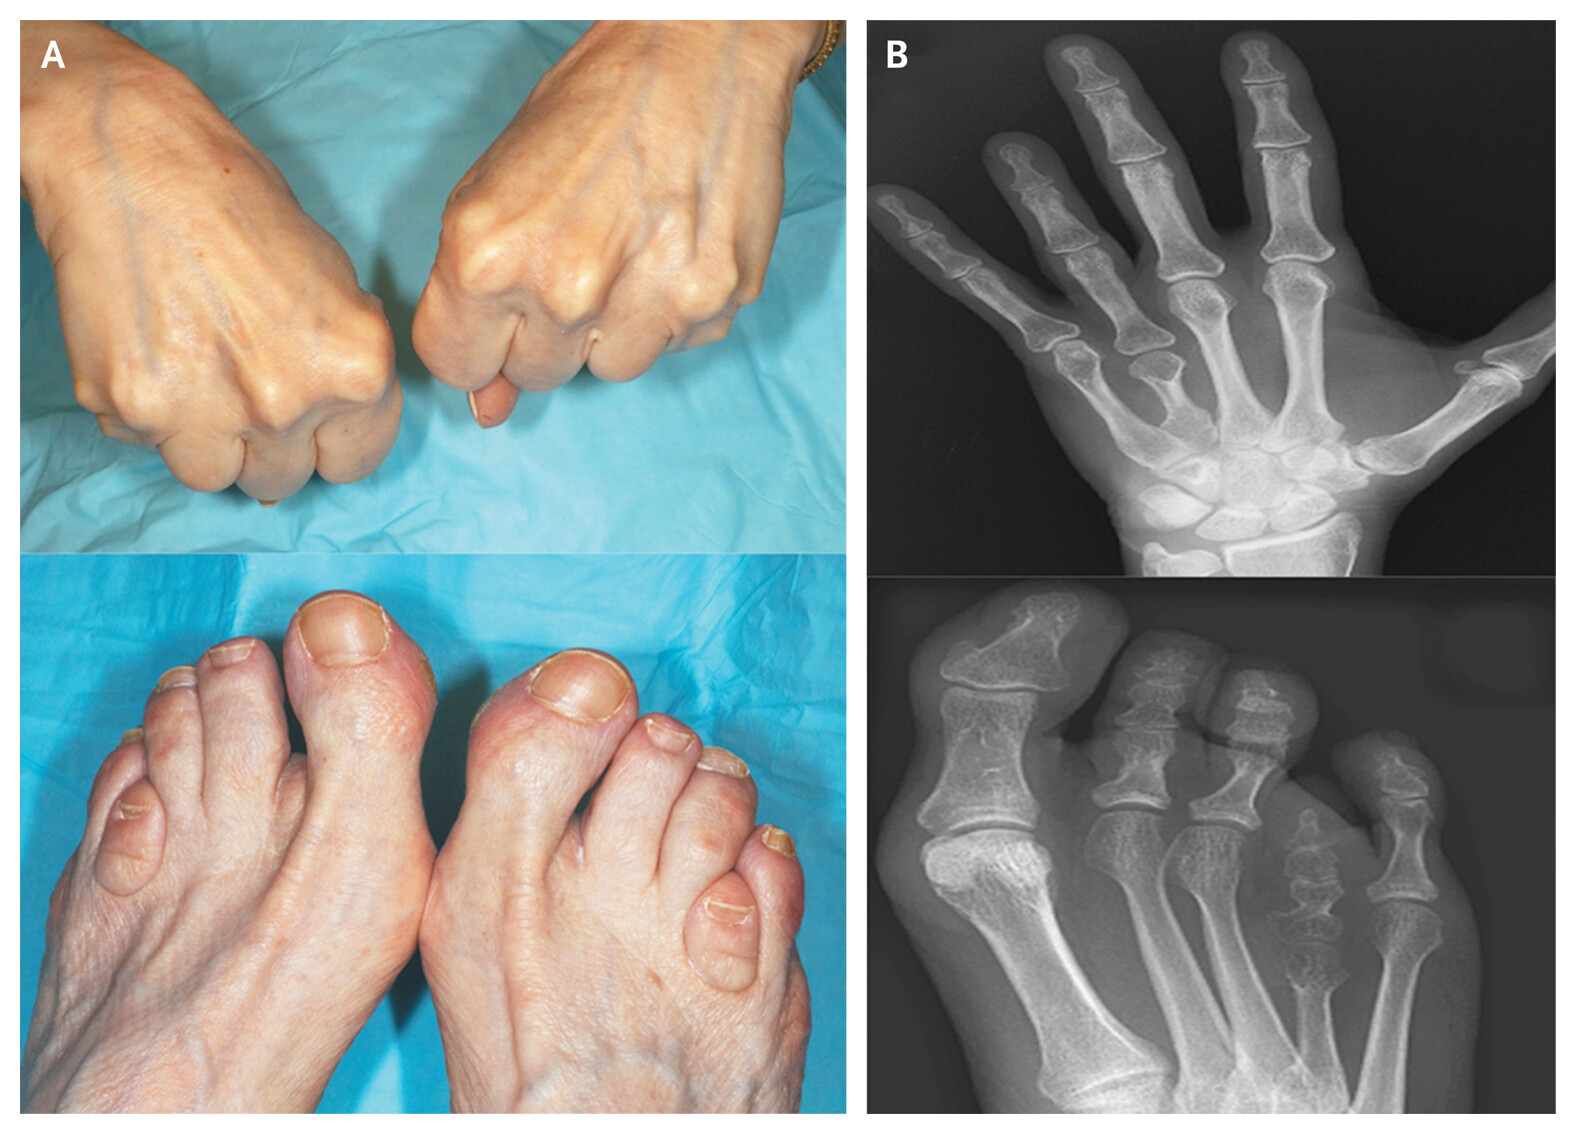

또한 특징적 외모 (Albright hereditary osteodystrophy)가 나타나는데

작은 키

둥근 얼굴

짧은 목

짧은 손가락(특히 3, 4, 5번째 중수골 단축)

이러한 점들이 특징적입니다.

임상에서는 저칼슘혈증 증상과 특징적 체형이 진단 단서가 됩니다.